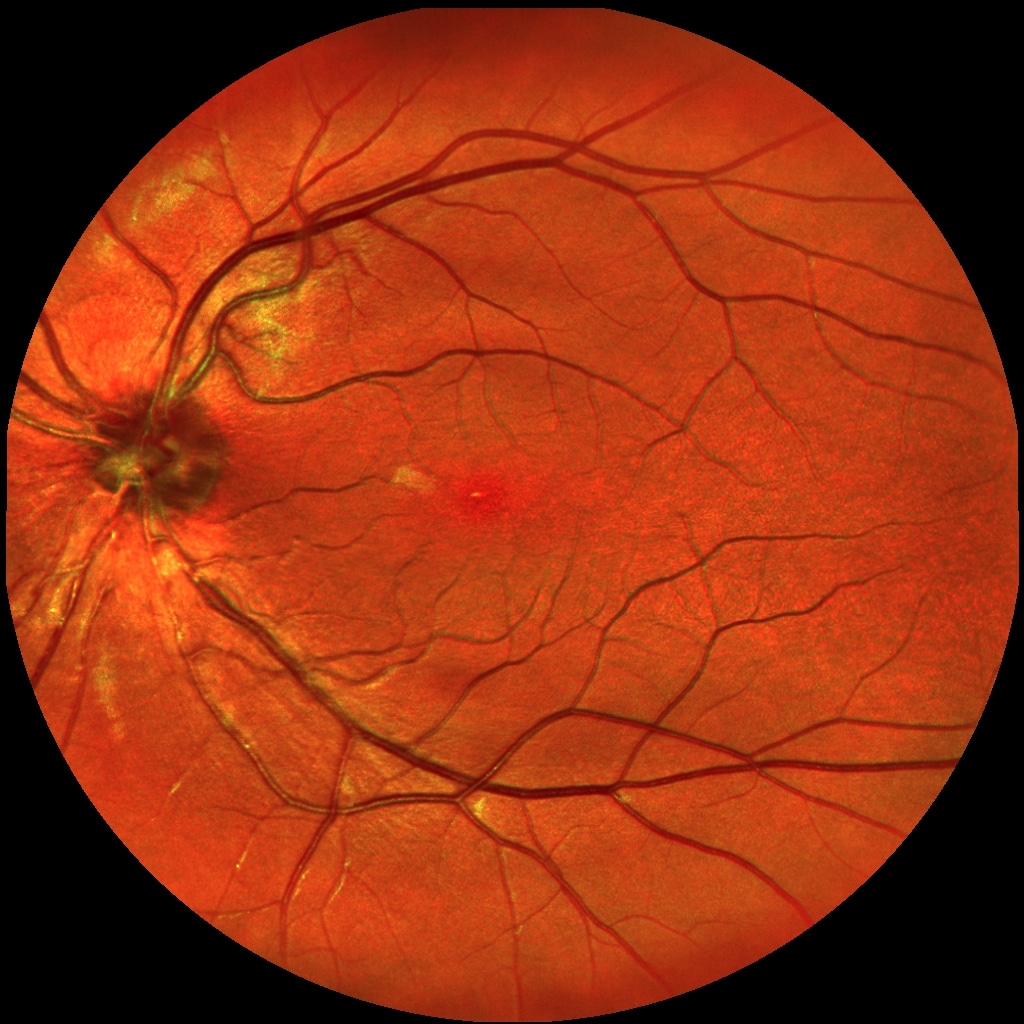

Gesunde Makula

Rechts:

Defekte Makula

Durch eine Makuladegeneration verliert man nach und nach die Sehfähigkeit im Bereich des schärfsten Sehens – der sogenannten Makula oder dem „Gelben Fleck“ (Fachbegriff „Makula lutea“) im Zentrum der Netzhaut. Dieser Bereich ist entscheidend, um zu lesen, Auto zu fahren oder Gesichter zu erkennen.

Bei der altersbedingten Makuladegeneration (AMD) ist der Stoffwechsel der Netzhaut gestört, wodurch sich Abfallprodukte, sogenannte Drusen, ansammeln und die Versorgung der Netzhaut behindern.

• Trockene AMD: Lichtempfindliche Zellen werden langsam zerstört; Pigmentveränderungen können ein Hinweis auf die Erkrankung sein.

• Feuchte AMD: Neue, undichte Blutgefäße wachsen unter die Netzhaut, führen zu Flüssigkeitseinlagerungen und schädigen die Zellen.